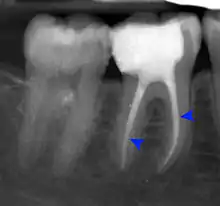

The periodontal ligament becomes inflamed and there may be pain when biting or tapping on the tooth. On an X-ray, bone resporption appears as a radiolucent area around the end of the root, although this does not manifest immediately.[10]:228 Acute apical periodontitis is characterized by well-localized, spontaneous, persistent, moderate to severe pain.[6]:125–135 The alveolar process may be tender to palpation over the roots. The tooth may be raised in the socket and feel more prominent than the adjacent teeth.[6]:125–135

Decay (green) with apical abscess (blue)

Gutta-percha point indicating abscess origin